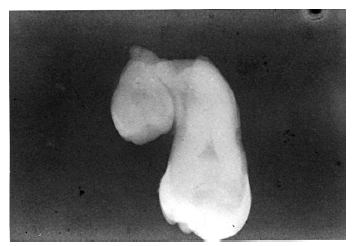

Fusion is defined as the joining of two originally separate teeth through the dentin, or through the dentin and enamel. In contrast, gemination represents incomplete division of what should have been two separate teeth. Fusion may involve supernumerary teeth, and gemination may occur in quadrants also affected by partial anodontia; thus, counting the teeth in the affected area is of limited diagnostic value. Regardless of which process initiated the error, it is practically impossible to distinguish between fusion and germination, and in either case, the tooth will appear much like that in Figure 40

The distinction between fusion and germination is primarily of academic interest and thus, the etiology is of less clinical concern than is the presence of the condition and the potential ramifications involved.

Figure 40 - Fusion or Gemination

Figure 40